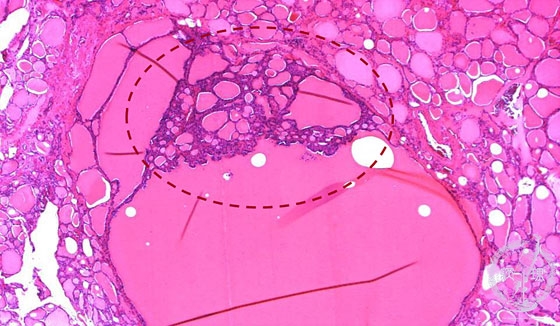

- (6)Nodular (adenomatous) goiter

Microscopic findings (HE stain, low power view): Projection of small follicles into large follicular space (dotted -line), also called “Sanderson polster”, is characteristic of nodular goiter.